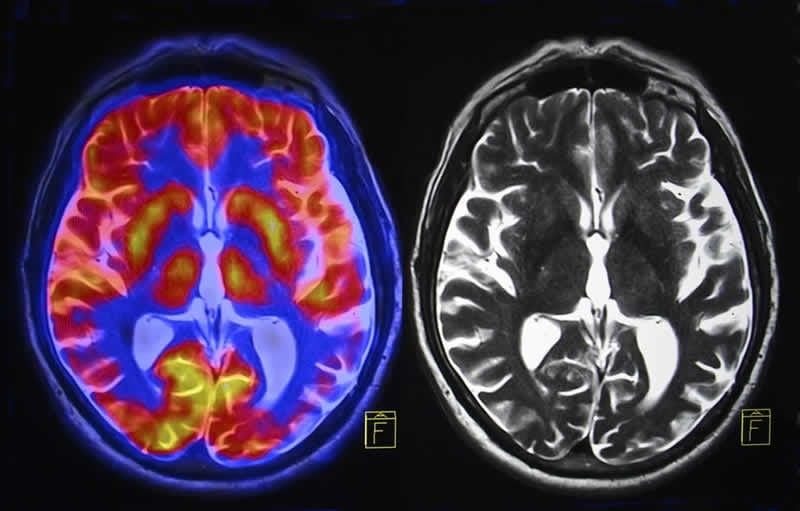

Brain Changes with Burnout